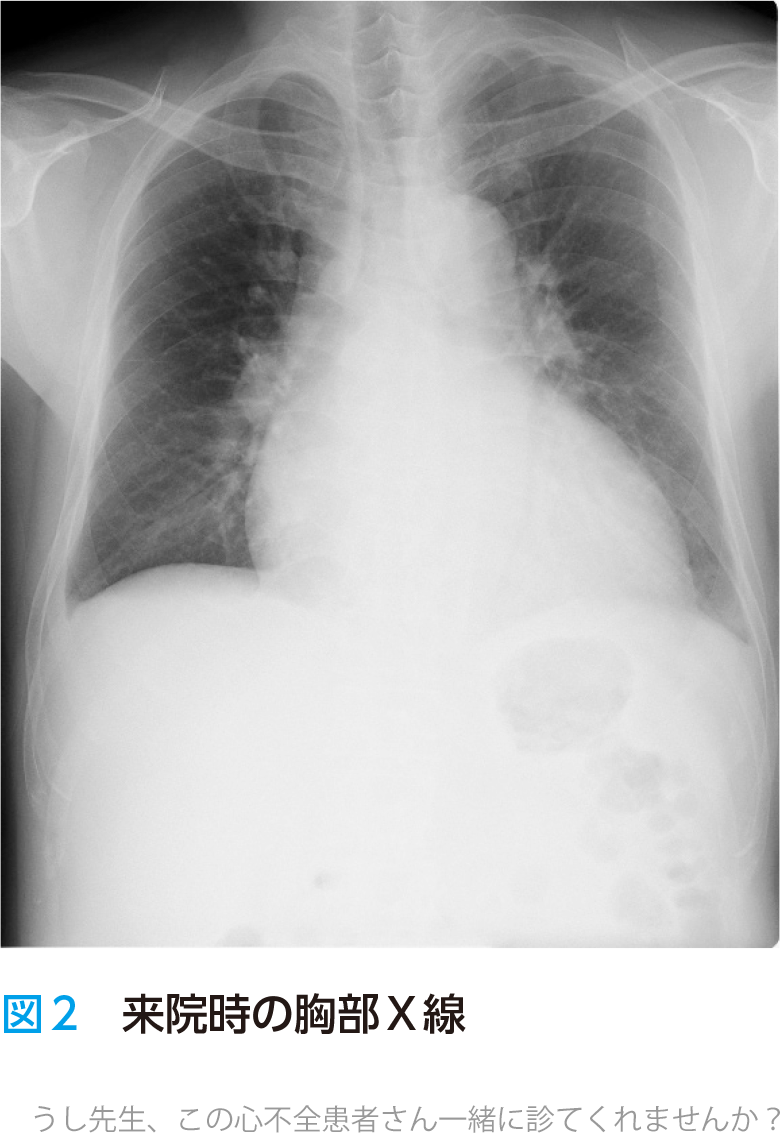

- 心電図(図1)と胸部X線(図2)を施行.